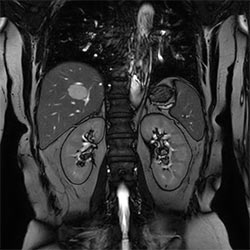

In a society where reimbursements are declining and chronic conditions lead to increased MR procedures and longer waiting times, there is ever increasing pressure on the radiology department. Today, further attempts to accelerate, compromise image quality or are limited to a narrow range of scans. Therefore, to meet the increased demand for productivity, a technology break-through in acceleration is still required. Leveraging our long standing leadership position in speed (i.e. SENSE), Philips brings compressed SENSE, a breakthrough in productivity.

Learn more about the main principles of Compressed SENSE and how it introduces a paradigm shift in productivity, how Compressed SENSE was designed around image quality, and how it advances productivity for clinical MR imaging.